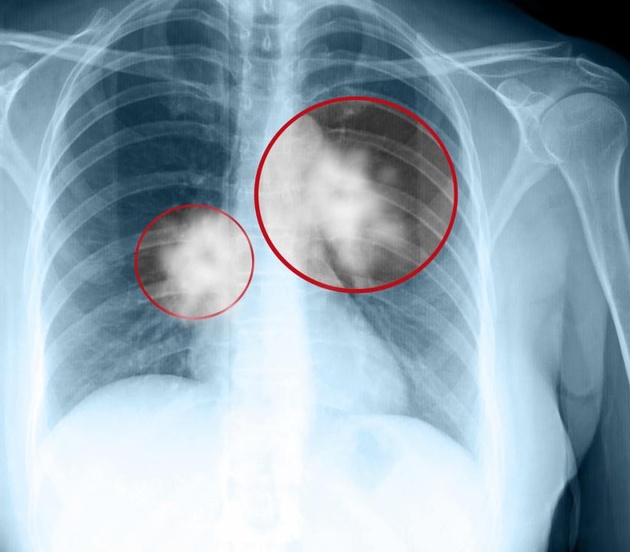

Cuba đã phát triển thành công và sở hữu một loại vắc-xin chống ung thư phổi. Mang cái tên Cimavax, nó có thể biến ung thư phổi giai đoạn cuối thành một bệnh mãn tính có thể kiểm soát.

Thay vào đó, Cimavax thúc đẩy cơ thể người bệnh sản xuất kháng thể chống lại một hooc-môn tăng trưởng biểu bì. Loại hooc-môn này thúc đẩy sự tăng trưởng tế bào, nhưng mặt khác khiến khối u lớn lên và mất kiểm soát. Kiểm soát được loại hooc-môn này, Cimavax có thể ức chế sự phát triển của ung thư phổi, hạn chế sự di căn của nó và biến ung thư chỉ còn là một bệnh mãn tính để điều trị.

Cimavax không tấn công trực tiếp khối u mà tăng cường hệ miễn dịch cơ thể.